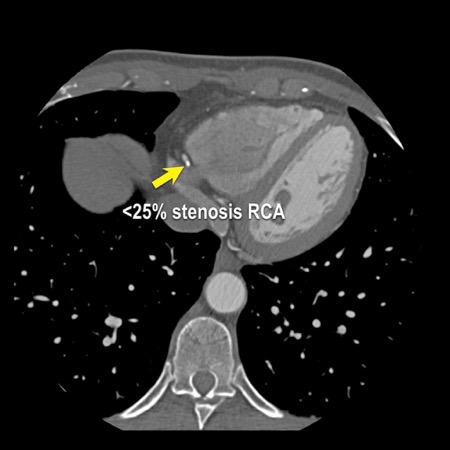

case 1 – CAD-RADS 2/P1

First, scroll through the scan.

Not all images are included. Some images without any abnormalities are skipped

from the series.

How would you describe the findings on the coronary CTA?

The findings are:

- Agatston score of

this patient was 14 (P1). Please, also note the calcification of the aortic valve. - Some partially

calcified and calcified plaques are present in the LAD with mild stenosis

(25-49%). - Calcified-plaque in

the LCX causing minimal stenosis (<25%). - Non-calcified

plaque in the distal RCA causing minimal stenosis (<25%). - This patient classifies

as CAD-RADS 2/P1, which means no further workup is needed.